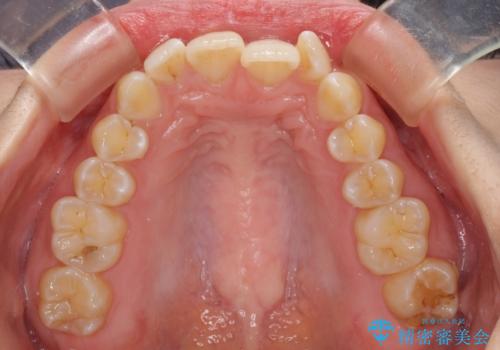

- 上下前歯のデコボコと深い咬み合わせを気にして来院された患者様です。

インビザラインによる上下歯列の拡大と、IPR(歯と歯の間を削る)にるスペースの獲得により、前歯のデコボコを改善することとしました。

上の前歯をもう少し整えたかったのですが、患者様の治療を早く終了させたいという希望により、細かい叢生を残しての終了となりました。